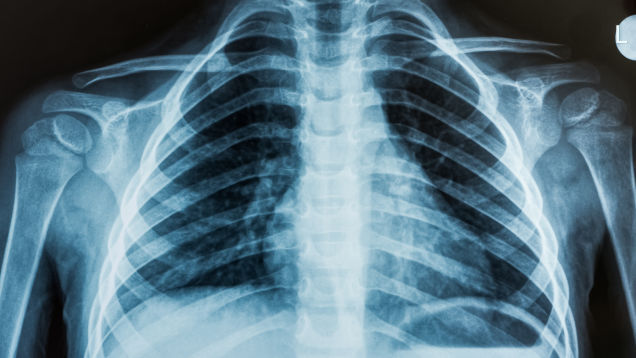

X-rays and other medical images are supposed to be private, since they are part of your medical records. But a recent ProPublica investigation found patients’ images just sitting around on the internet for anybody to view.

Source: LifeHacker – Your Private Medical Images May Online for Anyone to See